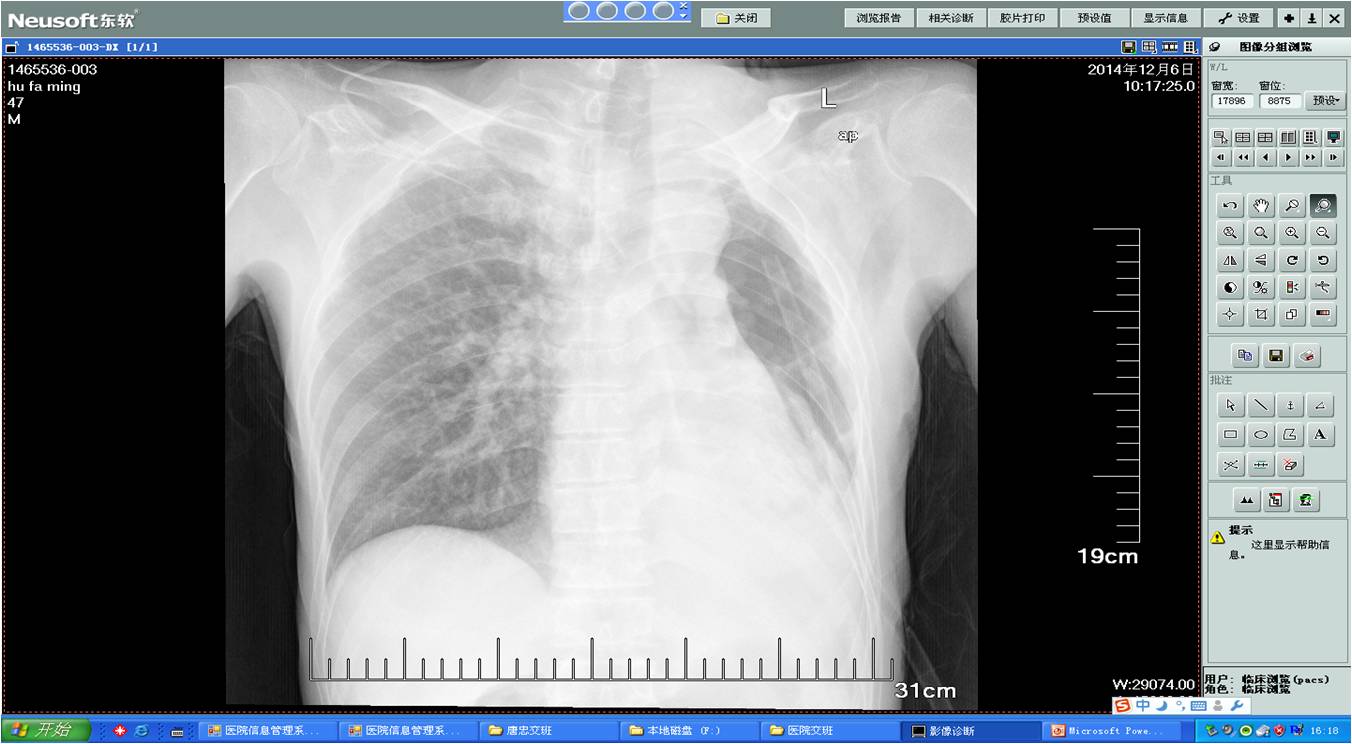

术后DR胸片

术前胸片

术前胸片